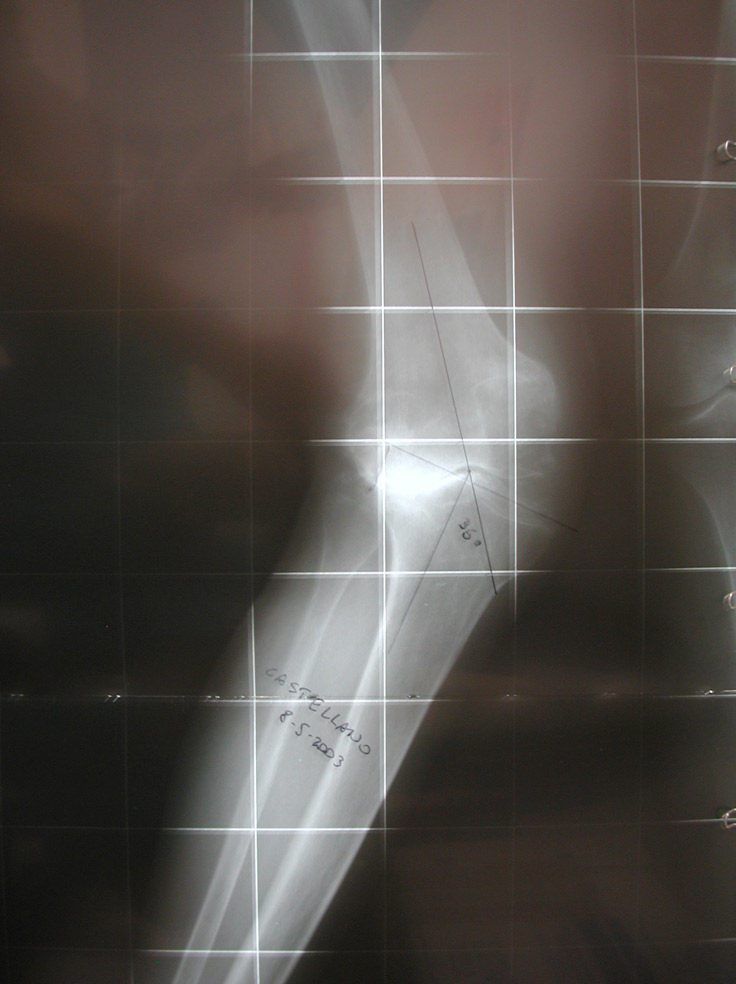

protesi ginocchio grave deformità

Caso clinico di paziente di 85 anni con artrite reumatoide e lussazione congenita d’anca controlaterale (deambulazione con rialzo di 6 cm), ormai costretta su una carrozzina a causa della grave deformità e instabilità del ginocchio destro. Questo caso dimostra che non esiste deformità che non possa essere corretta con un buon intervento di impianto protesico di ginocchio.

Fig. 1 radiografia preoperatoria che dimostra una deviazione in valgo di circa 40° del ginocchio destro con grave perdita di sostanza ossea del piatto tibiale laterale